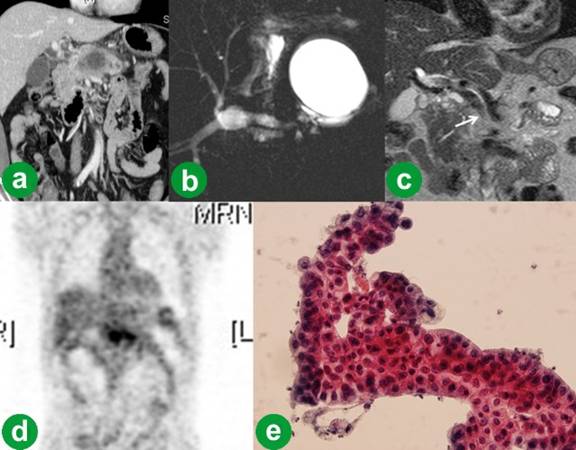

A 52-year-old male patient was admitted for abdominal discomfort and weight loss over the previous year. He was a heavy consumer of alcohol and was hospitalized with suspicion of a pancreatic pseudocyst with chronic pancreatitis without tenderness or palpable mass in his abdomen and diabetes mellitus. The results of his laboratory investigations were unremarkable except for his serum levels of glucose (169 mg/dL; reference range: 70-110 mg/dL), carcinoembryonic antigen (5.37 ng/mL; reference range: 0-5.00 ng/mL) and carbohydrate antigen (CA) 19-9 (210 U/mL; reference range: 0-37 U/mL) which were all elevated. Computed tomography (CT) revealed aggravation of the cystic lesion (about 5.5 cm in size) and diffuse inflammation around the pancreatic parenchyma with pancreatic duct dilatation (Figure 1a). A magnetic resonance cholangiopancreatography (MRCP) demonstrated a large unilocular cyst at the head without communication with the main pancreatic duct (Figure 1b). Magnetic resonance imaging (MRI) revealed a stenosis of the superior mesenteric vein-portal vein junction (Figure 1c). Positron emission tomography (PET) showed hypermetabolism at the pancreatic head area, suggesting pancreatic cancer (Figure 1d). Endoscopic ultrasound (EUS) with fine-needle aspiration of the cyst was then performed. Histopathological analysis of the cystic fluid revealed an atypical epithelium with intracytoplasmic mucin, suggestive of mucinous adenocarcinoma (Figure 1e). In addition, immunohistochemical analysis of the fluid showed that amylase (1,927 U/L reference range: 30-115 U/L), lipase (13,688 U/L reference range: 5-60 U/L), carcinoembryonic antigen (925 ng/mL) and CA 19-9 (more than 20,000 U/mL) levels were all extremely high. Based on these findings, we diagnosed it as a mucinous cystadenocarcinoma involving the pancreatic head and body with superior mesenteric vein-portal vein invasion; we then decided to perform a total pancreaticoduodenectomy with a possible superior mesenteric vein-portal vein confluence resection.

Figure 1. Preoperative studies. a. CT revealed aggravation of the cystic lesion (about 5.5 cm size) and diffuse inflammation around the pancreatic parenchyma with pancreatic duct dilatation. b. MRCP demonstrated a large unilocular cyst at the head without communication with the main pancreatic duct. c. MRI revealed stenosis of the superior mesenteric vein-portal vein junction (arrow). d. PET showed hypermetabolism at the pancreatic head area, suggesting pancreatic cancer. e. Histopathological analysis of the cystic fluid revealed an atypical epithelium with intracytoplasmic mucin, suggestive of mucinous adenocarcinoma. |